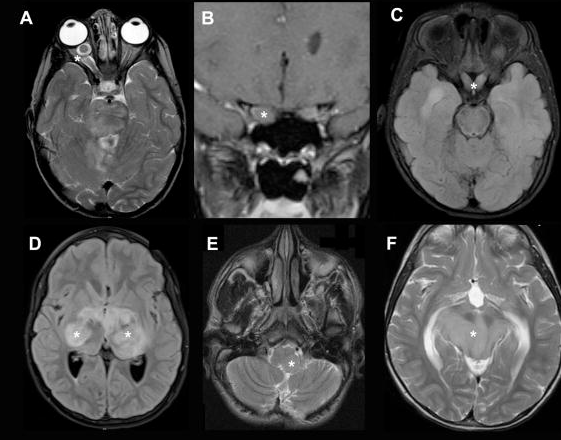

一名6岁的女童在视力检查出现问题后被转介到眼科。经检查,她的左眼视力下降(20/80)和色觉(仅限控制板)。右眼视力和色觉正常。她有一个低振幅,高频摆...

分离到视神经神经胶质瘤(ONG)是视神经胶质瘤的一个亚组,其治疗仍有争议。大多数视神经胶质瘤存在某种形式的视觉症状,这些症状由肿瘤的位置决定...

视神经胶质瘤如何治疗?肿瘤的大小和程度会影响肿瘤的表现,从单纯的视神经胶质瘤到更大的外生肿瘤,并延伸到下丘脑、垂体、三脑室和间脑。内分泌...

视神经胶质瘤能治好吗? 视神经胶质瘤(optic pathway glioma,OPG)是少见的颅内肿瘤之一。主要临床表现为视力下降、视野缺损及眼球突出等,病变累及下丘脑...

视神经胶质瘤是什么病? 视神经胶质瘤是发生于视神经和累及视交叉内胶质细胞的原发性肿瘤,由于视神经是胚胎期前脑向外分化形成,属于中枢神经系统...